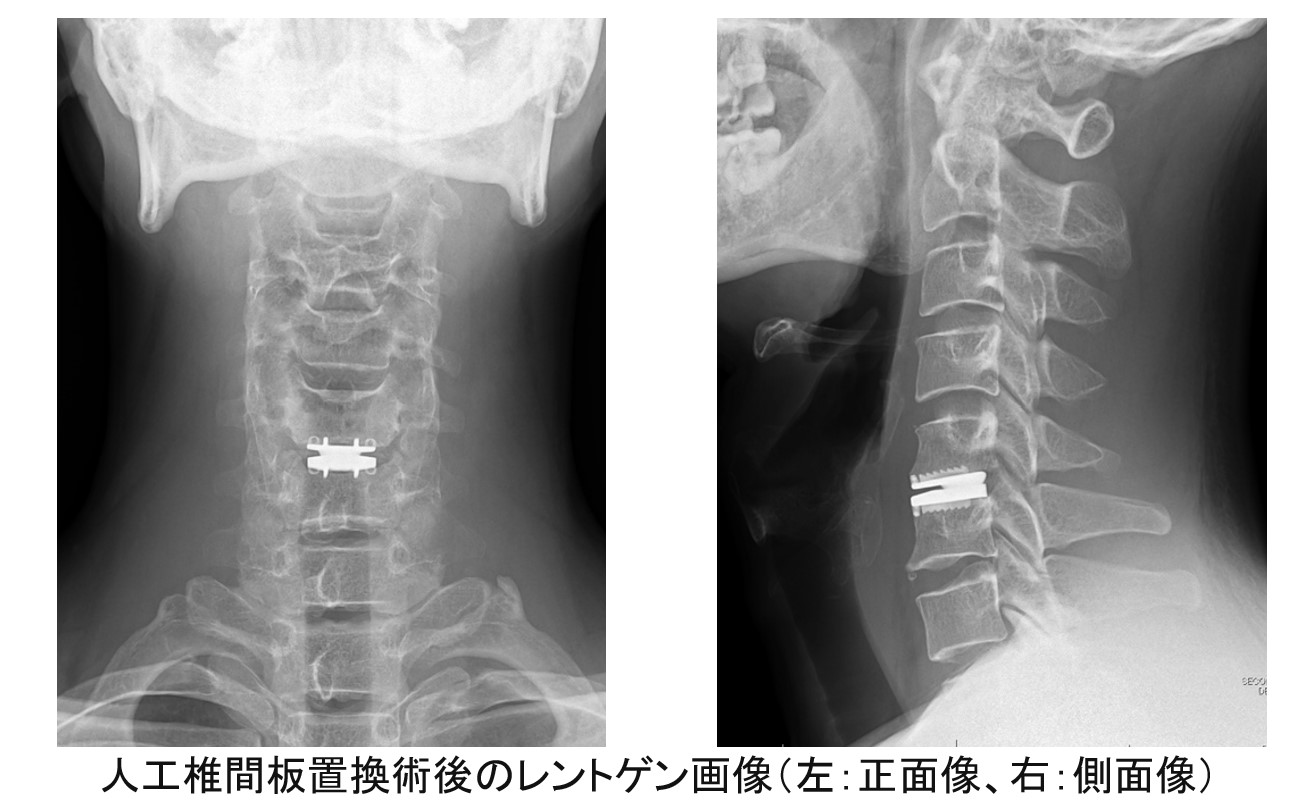

手術は多くの場合、首の前方から椎間板や骨棘を切除した後、人工骨などを移植してインプラントで固定する『前方除圧固定術』が行われます。ただし『前方除圧固定術』は本来の首の動きを犠牲にするため、固定した箇所の隣の椎間に新たな障害が発生しやすくなるという欠点があります。そこで最近では適切な患者さんに限り、椎間を固定するのではなく、首の動きを温存するインプラントに置き換える『人工椎間板置換術』も行っています。